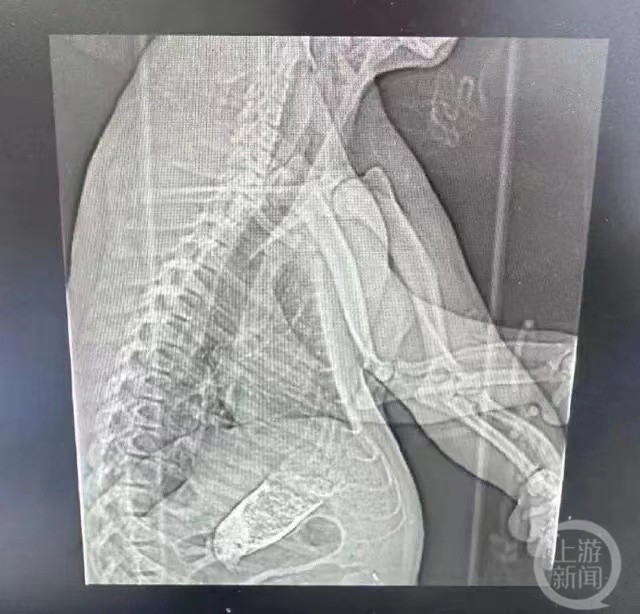

▲经检查,“七七”患有肠梗阻。图片来源/受访者供图

2月27日,“七七”被送往上海仁济医院进行胸腹部CT检查,CT报告确诊“七七”肠梗阻。工作人员表示,经专家会诊已形成治疗意见,决定对“七七”实施手术。

▲“七七”正在做CT检查。图片来源/受访者供图